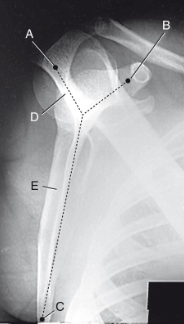

label 1-9 accordingly

1. Acromion

2. Humeral head

3. Greater tubercule

4. Anatomical neck

5. Lesser tubercule

6. Surgical neck

7. Clavicle

8. Coracoid process

9. Glenoid cavity

without labeling, this is the anatomy of what kind of x-ray? (projection and body part)

scapular Y lateral

label 1-7 accordingly

1. AC joint

2. Acromion

3. Scapular spine

4. Humeral head

5. Body of scapula (superimposed over

humerus)

6. Clavicle

7. Coracoid process